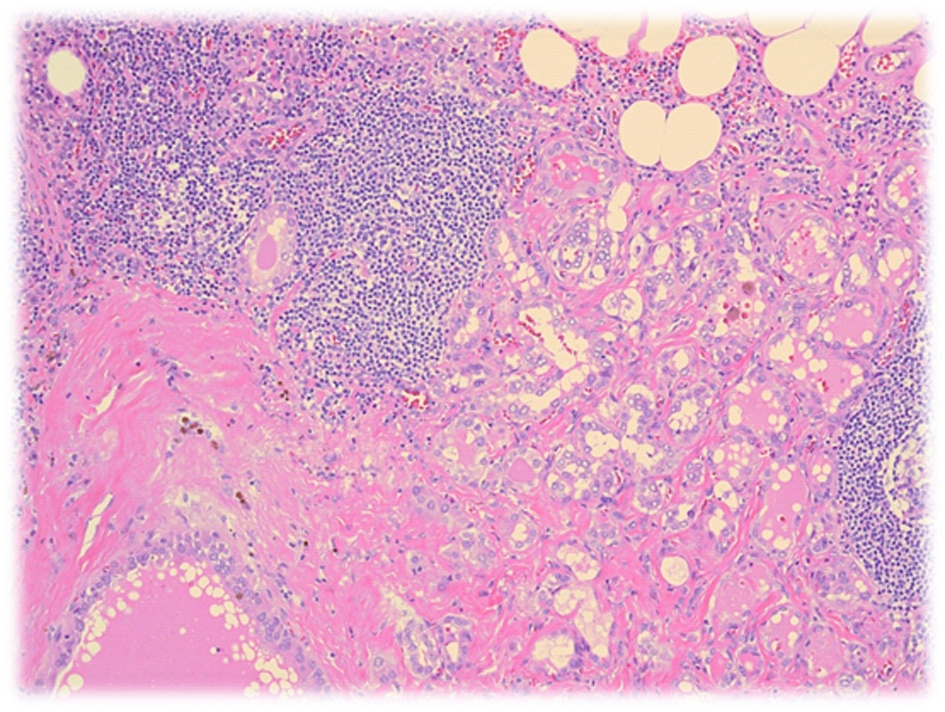

Карнификация Легкого: Микропрепараты и Диагностика

Раздел: Калейдоскоп образов